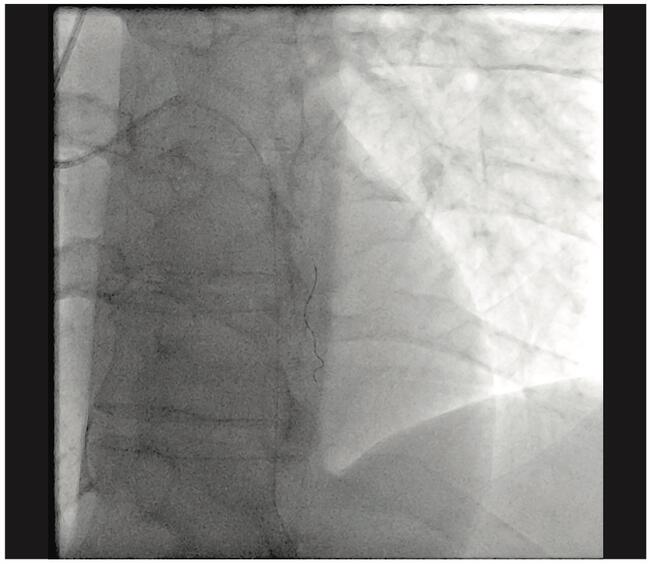

Successful Stenting Using Low-Dose Angiography With Asymmetric Edge Enhancement

This case involving a stenting procedure demonstrates how low-dose angiography can yield optimal image quality to increase clinical certainty during patient interventions. A 48-year-old male was referred following a positive stress test that indicated anterior ischemia as well as prior stent implantation. Cardiac images were obtained (via the ARTIS Q ceiling-mounted angiography system with CLEAR MAX technology from Siemens Healthineers) and provided asymmetric edge enhancement to the vessel while maintaining As Low as Reasonably Achievable (ALARA) dose levels. The images revealed a first diagonal narrowing of approximately 90% at the ostium with good distal flow. The patient then underwent a successful percutaneous coronary balloon and stenting procedure. An observed reduction in case time was attributed largely to the improved image quality from the applied asymmetric edge enhancement.